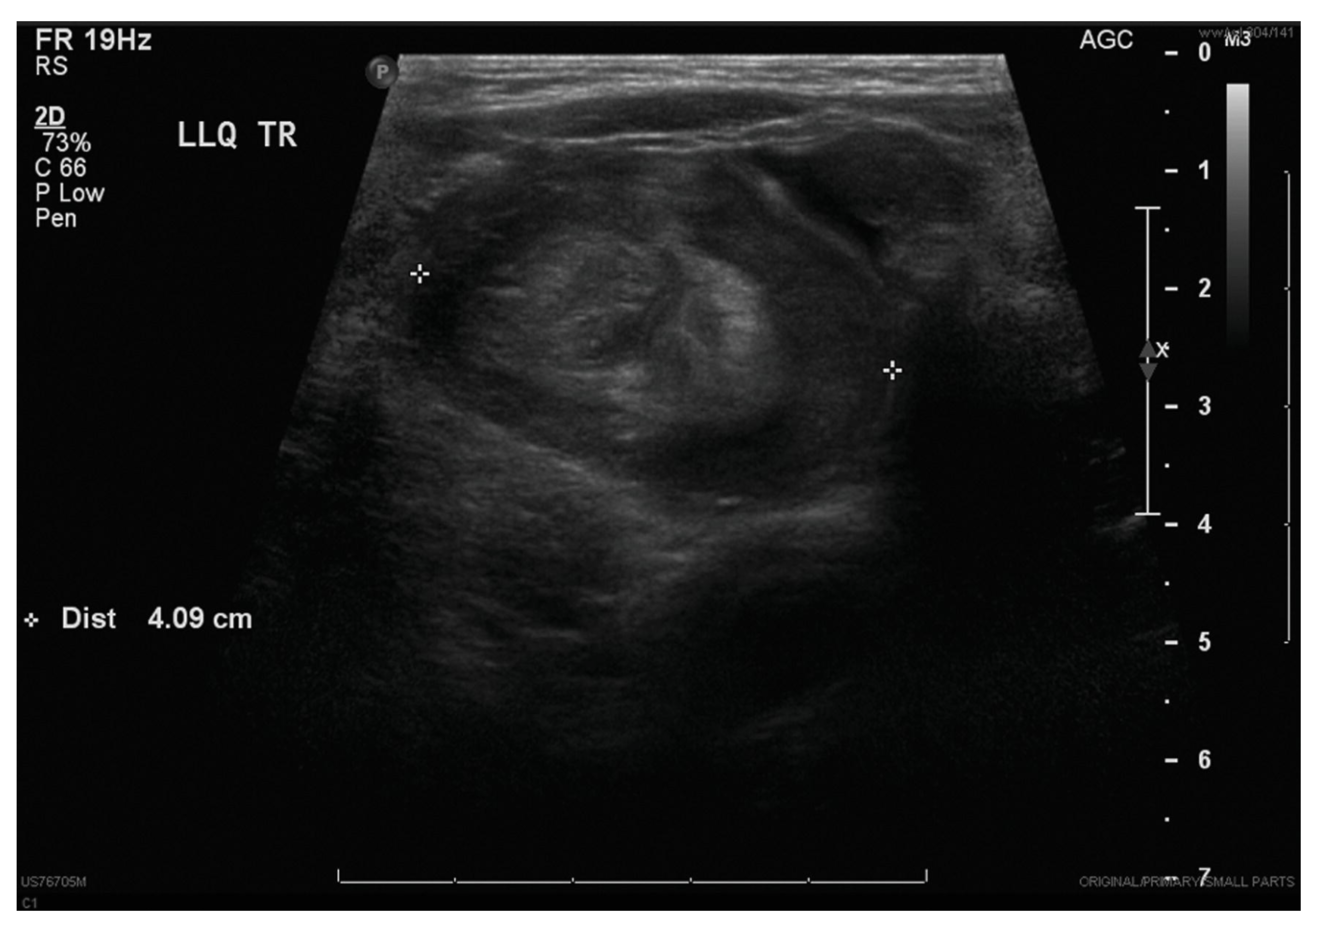

U/S looking for SMV to the left or anterior to SMA

Diagnostic work up for RLQ pain in child (intussuception)

Ultrasound, target sign